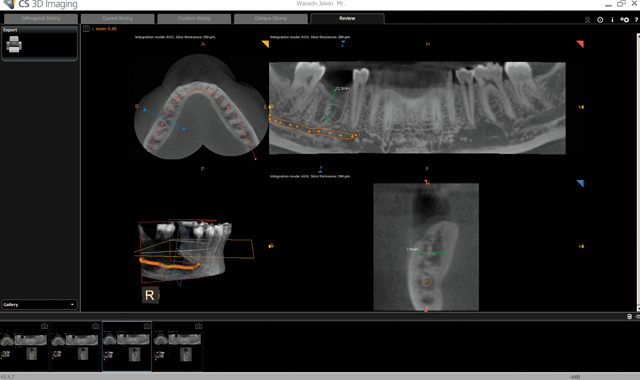

Fig. 6 Surgical guide to ensure predictable prosthetic results

From there, I can send the scans to a lab to merge the data files to make a surgical guide (Fig. 6). Both my CBCT and intraoral files are open-format (DICOM and STL, respectively), so I can send this information to the laboratory of my choice for fabrication. Merging CBCT and digital impressions is quickly streamlining dental implant surgery as well as improving accuracy of the results.3

Depending on what I see in the CBCT scan, I can order a surgical guide with pilot drills or a fully guided surgical guide that includes position, angle and depth. This is beneficial in a lot of ways, including having the ability to confidently perform the treatment plan as well as to obtain predictable results.